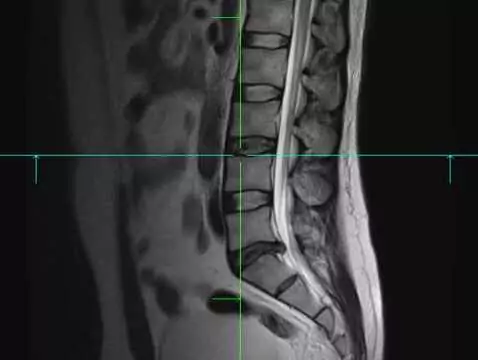

Una discopatía, se define como el estado inicial de una enfermedad degenerativa de la columna vertebral. Cuando una discopatía no se trata, progresa muy rápidamente. Una discopatía, se define como un...

Una discopatía no es más que el prolapso de un disco intervertebral de su lugar, su posición natural. En la mayoría de los casos, las discopatías suelen afectar a la parte inferior de la columna...